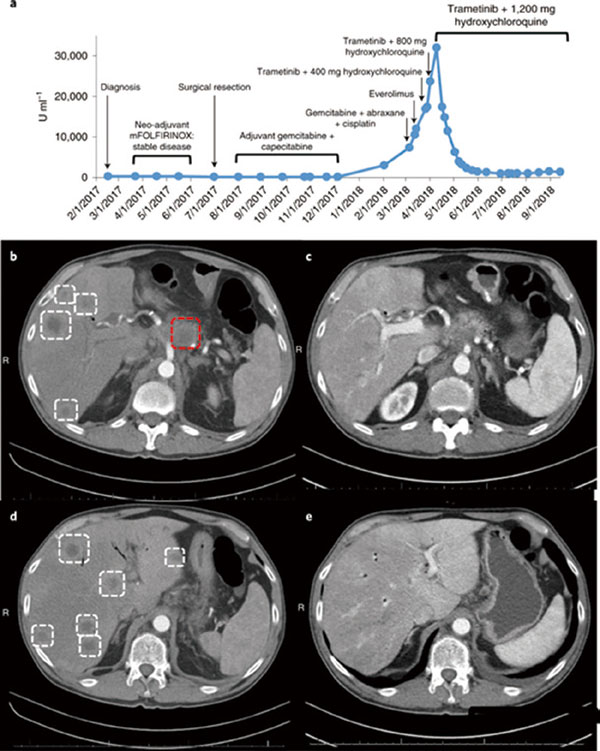

研究者在小鼠中进行了实验,单用氯喹、羟氯喹(也是一种自噬抑制剂)或曲美替尼,都不能抑制种植在小鼠身上的胰腺癌的生长,而联合使用曲美替尼和氯喹/羟氯喹,则几乎让肿瘤完全消失,效果好过治疗胰腺癌的标准方案(吉西他滨+白蛋白结合型紫杉醇)。

除了胰腺癌,研究者还在一些其他肿瘤中,试验了曲美替尼+氯喹的治疗效果。对携带NRAS突变的黑色素瘤小鼠和携带BRAF突变的结直肠癌小鼠,曲美替尼+氯喹同样显示良好的效果。治疗副作用也十分小,甚至都未出现体重下降。